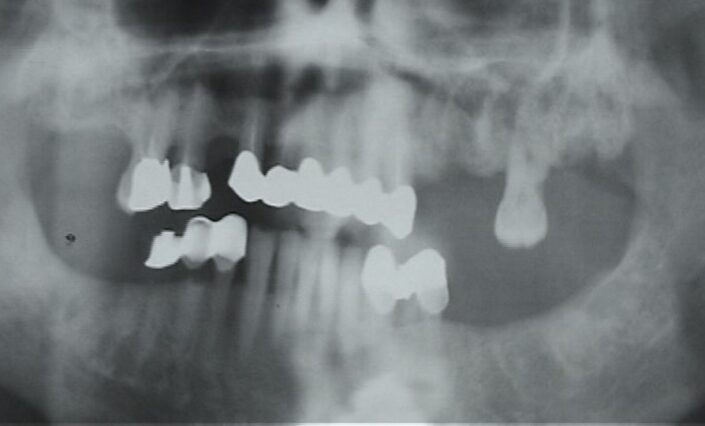

Radiologica:

OPT

Segni precoci:

- Ispessimento cresta alveolare e lamina dura

- Persistenza alveolo post-estrattivo

- Sequestro

- Allargamento spazio parodontale

Segni tardivi:

- Frattura patologica

- Ispessimento canale osseo Nervo Alveolare Inferiore

- Osteosclerosi diffusa

- Radiopacità seno mascellare

- Reazione periostale